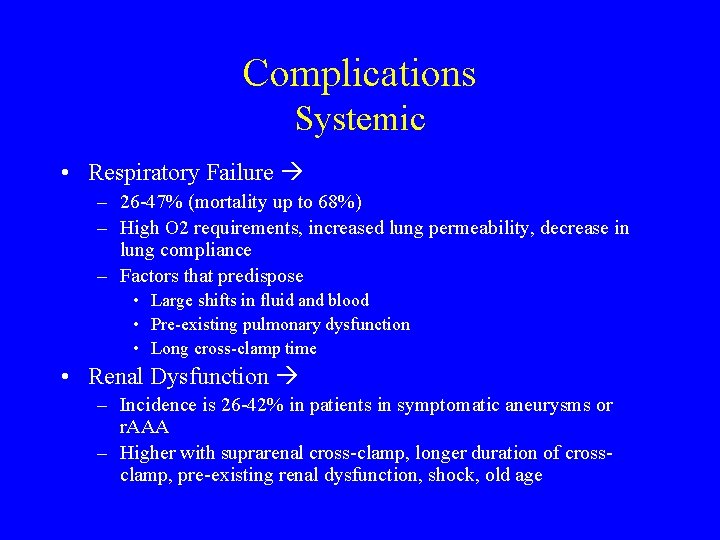

Complications Systemic • Respiratory Failure – 26 -47% (mortality up to 68%) – High O 2 requirements, increased lung permeability, decrease in lung compliance – Factors that predispose • Large shifts in fluid and blood • Pre-existing pulmonary dysfunction • Long cross-clamp time • Renal Dysfunction – Incidence is 26 -42% in patients in symptomatic aneurysms or r. AAA – Higher with suprarenal cross-clamp, longer duration of crossclamp, pre-existing renal dysfunction, shock, old age